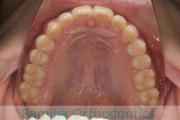

No.23V-385

- 主な症状:

- 叢生

- 年齢:

- 17歳

- 性別:

- 女性

- 抜歯部位

- 上:

- 44

- 下:

- 8448

- 主な使用装置:

- FEA 022

- 治療にかかった費用:

- 90万円

前歯のゆがみ、ズレがあるのを治したいということで来院されました。上下左右から小臼歯を抜歯して、マルチブラケット法にて治療をしました。1年8か月、20回程度の通院をしていただきました。叢生(でこぼこ、凹凸、ガタガタ)が強いため、保定をしっかりしないと後戻りのリスクがやや高いケースといえます。

- ≫治療前

-

上顎

下顎

前歯の関係など